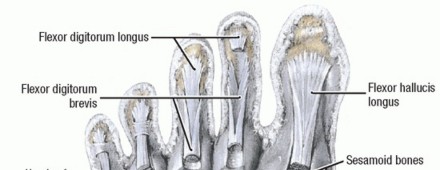

Dynamic Restraints

The most powerful extension force on the MTP joint is delivered by the extensor digitorum longus (EDL) tendon. The EDL extends the MTP joint through a fibroaponeurotic sling that attaches plantarly to the plantar plate and capsule, effectively suspending the proximal phalanx.

Flexion of the MTP joint is primarily governed by the intrinsic muscles (lumbricals and interossei). The second toe possesses a unique anatomical vulnerability: it has two dorsal interossei and zero plantar interossei.

Static Restraints

The primary static stabilizers of the MTP joint are the collateral ligaments and the plantar plate. The plantar plate is a robust, fibrocartilaginous structure that originates on the metatarsal neck and inserts firmly into the plantar base of the proximal phalanx. Chronic joint irritation, effusion, and synovitis cause attritional degeneration, lengthening, and eventual rupture of these structures—most notably the lateral collateral ligament and the distal insertion of the plantar plate.

Originally described for flexible hammer toes, the transfer of the flexor digitorum longus (FDL) to the extensor mechanism is exceptionally effective at providing dynamic plantarflexion stability to an incompetent MTP joint. By rerouting the FDL dorsally, the procedure converts a flexor of the distal interphalangeal (DIP) joint into a dynamic plantar flexor of the MTP joint.

* Inspect the wound to ensure the two lateral slips of the flexor digitorum brevis (FDB) remain intact.

* Inspect the delivered FDL tendon to identify the shallow, linear furrow running longitudinally along its plantar surface.